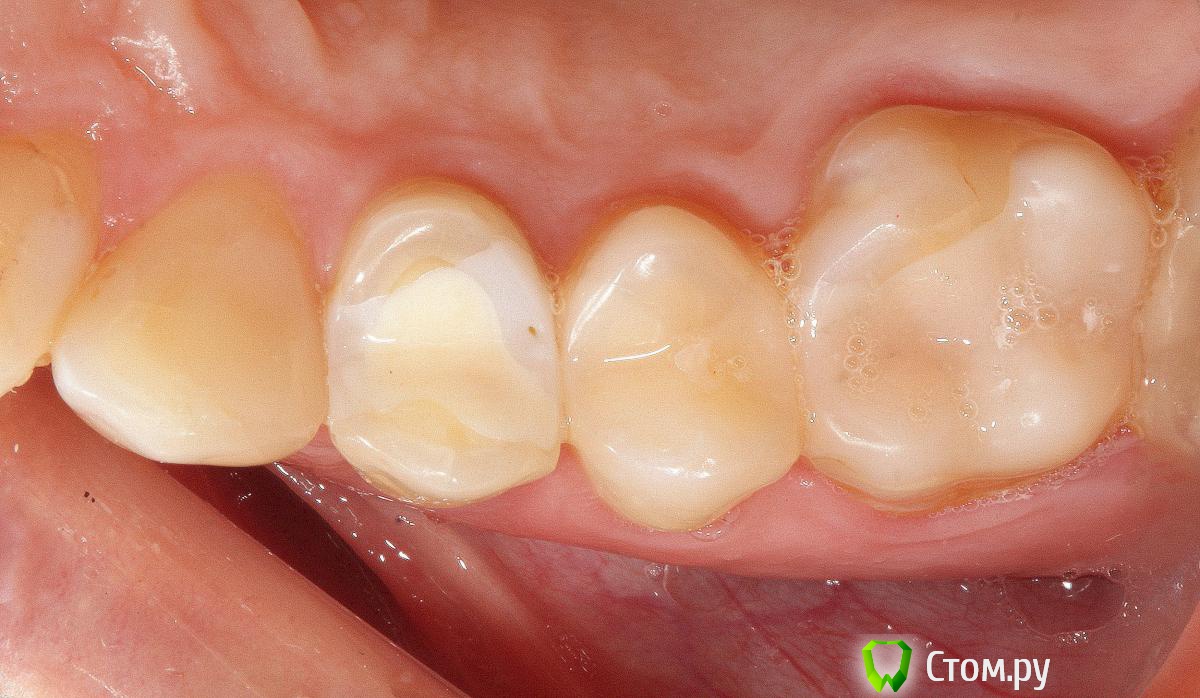

SDC Опубликовано 19 ноября, 2014 Поделиться Опубликовано 19 ноября, 2014 (изменено) Prettau, извините, не знаю, как редактировать название темы. Здравствуйте всем. В хирургическом много практиков, а по протетике - много теории)). Итак, разбавляю вино. (теория вечна)Протезирование премоляров коронками Преттау с нанесением керамики вестибулярно.Много фото, прошу прощения, поэтому без радикала, превью. Наверное даже так лучше, потому, что по клику откроются не сжатые фото, а радикал жмет.Протезирование в течение 2 недель. Фиксация на фуджи, без коффердама, но в сухих условиях (коффер не поставить по причине глубокий дистальной границы препарирования на обоих премолярах - глубокий кариес проксимальных поверхностей в анамнезе)Рг-контроль на предмет остатков цемента и на последнем фото удаленные излишки цемента на перчатке. Изменено 19 ноября, 2014 пользователем SDC 7 Ссылка на комментарий